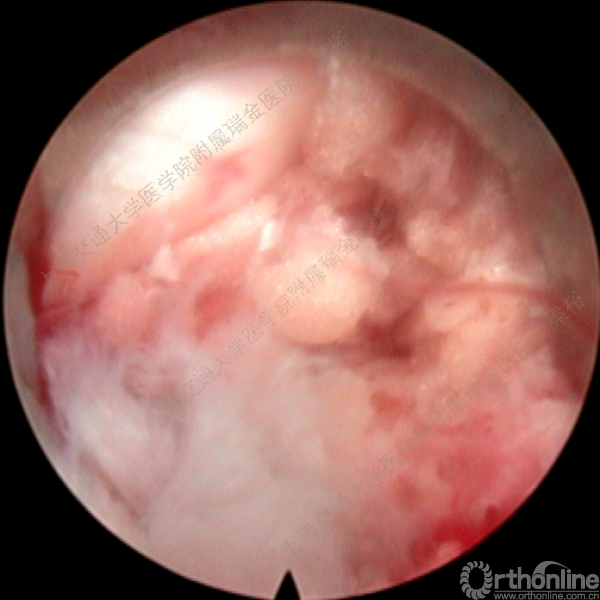

随着微创技术的发展以及手术经验的积累,脊柱微创手术已开始逐步取代传统的脊柱外科手术。微创手术已涉及从颈椎到腰椎的整个脊柱。从简单的椎间盘手术到复杂的 脊椎手术,手术类型越来越多样。在所有的脊柱微创手术中,尤其脊柱内镜手术在过去10年中取得了惊人的进步。在技术发展的同时,脊柱内镜的手术并发症问题也逐渐浮出了水面,针对脊柱内镜手术的并发症与其对策,上海交通大学医学院附属瑞金医院梁裕教授介绍了他们的经验。